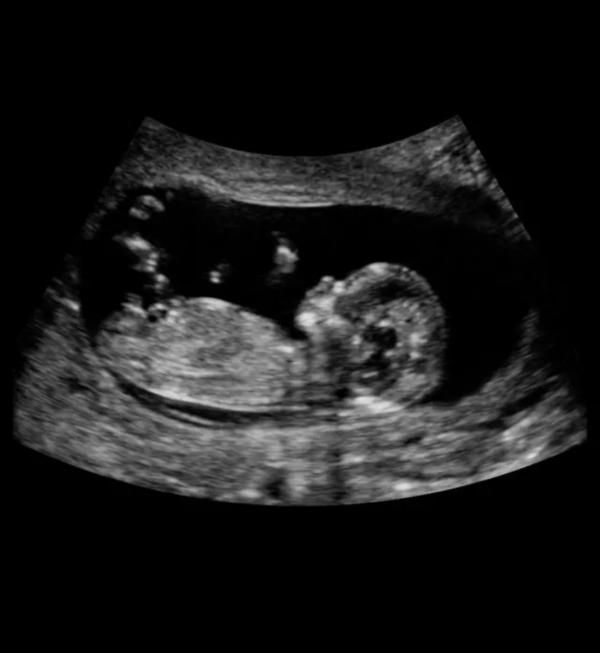

Что ж, надеюсь я с ума не сойду с погодками. Не ожидала, не ожидала... Первое узи и уже 12 нед оказалось, успела на скрининг как раз😄. Если бы не мой токсикоз наверное и не узнала бы о беременности.

Ваув 😅МашАллагь ❤️представляю ваш шок, уже целый человечек там 😍

Ничего себе , аж 12 недель 🥰 пусть малыш растёт и крепнет 🤲🏻

Пол не спросила пока. Я не знала срок, пошла на первое узи, оказалось 12 нед